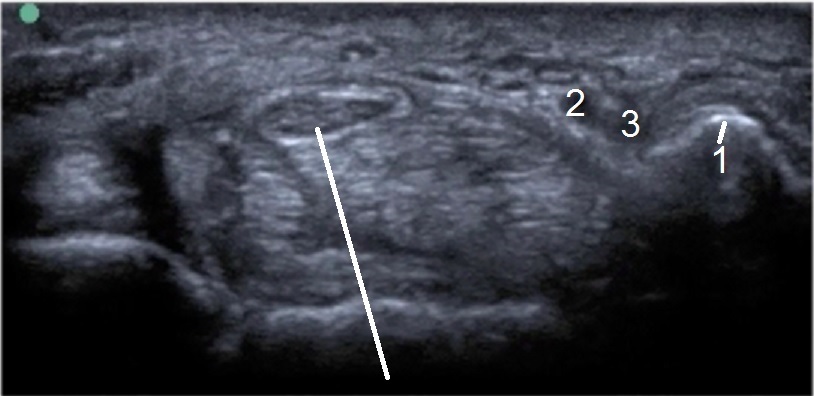

手首の手根管の解剖2の画像

豆状骨

尺骨動脈

尺骨神経